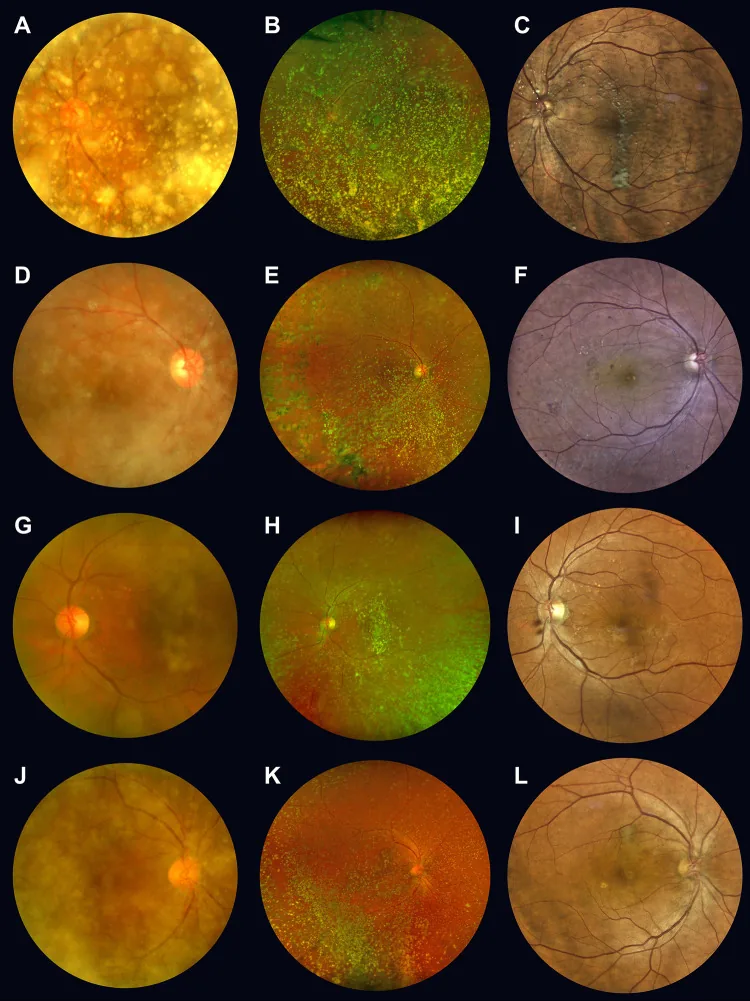

星状硝子体症(Asteroid Hyalosis; AH)は、一般に60歳以上の高齢者にみられる硝子体線維の変性疾患である。星状体(asteroid body; AB)が硝子体のコラーゲン線維内に沈着し、硝子体の変性を生じると考えられている。星状体はカルシウム含有リン脂質・ムコ多糖(またはリン酸カルシウム)が主体であり、黄白色で球状の粗な粒子が硝子体中に浮遊する。眼球運動とともに可動性を呈するが、静止すると元の位置に戻る。

通常は無症状である。中等度の混濁があっても飛蚊症を自覚しないことが多く、視力は良好で治療不要なことが多い。高度混濁でも視力が保たれていることが特徴であり、眼底の観察が困難なほどの高度な星状硝子体症でも視力良好で治療が不要なことが多い。

細隙灯顕微鏡による前部硝子体の観察は必須である。眼球を動かしてもらい、硝子体の動きを観察する。細隙灯顕微鏡では、黄白色で球状の粗な粒子が硝子体中に浮遊する所見を認める。

眼球運動とともに可動性を呈するが、静止すると元の位置に戻る。これは硝子体が液化していないため、星状体が硝子体線維に固着したまま動きに追随する現象である。星状体は大きな粒子であり、白血球との区別は容易である。

細隙灯顕微鏡による前部硝子体の観察は必須である。眼球を動かしてもらい、硝子体の動きを観察することで診断ができる。硝子体中の特徴的な黄白色球状混濁を確認し、眼球運動で可動性を示しながら静止で元位置に戻る所見が診断の鍵となる。カルシウム結晶由来の大きな粒子であり、診断は比較的容易である。